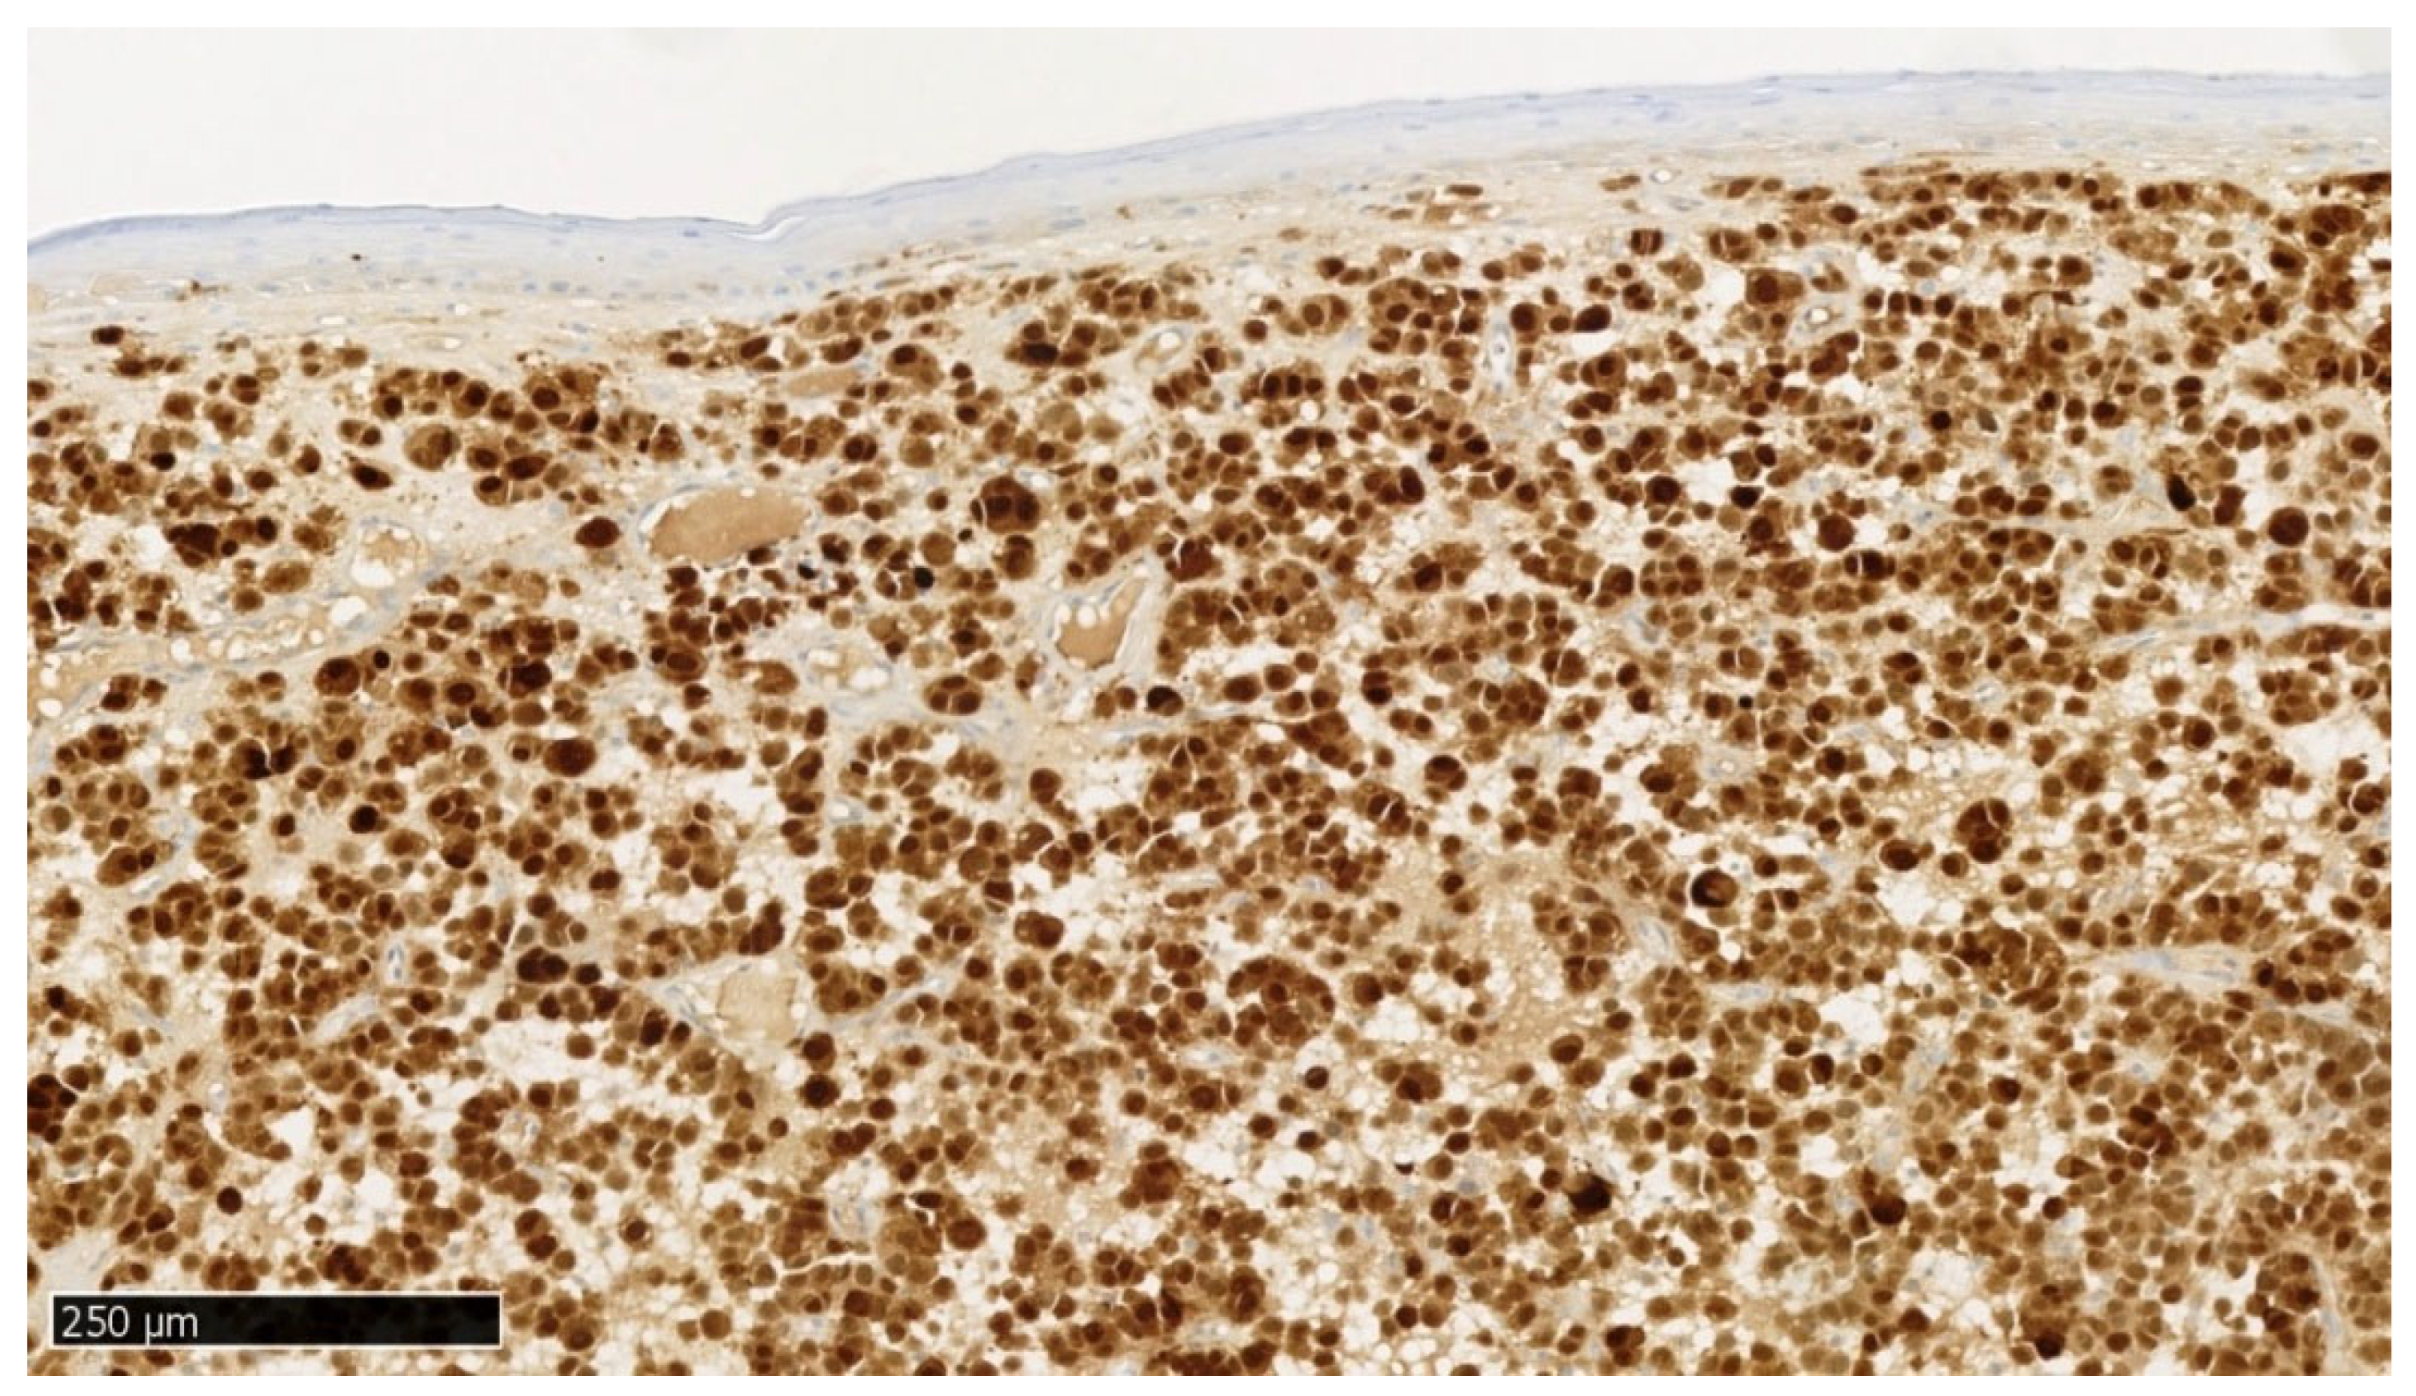

Histopathological examination result of the mandibular tumor: lower gingiva. Malignant melanoma within the oral mucosa (OMM). The entire polypoid tissue fragment sent for examination was occupied by neoplastic tissue, which undermined the covering stratified squamous epithelium. The neoplastic tissue reached the basal resection margin of the submitted tissue. Immunohistochemical studies: SOX10(+), MelanA(+), LCA(-), CK Pan(-), high proliferative index Ki67 – 70% confirmed the diagnosis of melanoma. Satellite nodules, features of regression, neuroinvasion, and angioinvasion: absent. Ulceration: present. Mitotic index: 5/mm2, including atypical mitoses. Lymphocytic infiltrates (TILs): present (non-brisk). Melanoma tissue is visible at the edges of the examined sections (surgical margin uncertain) (Figure 7–10).

Figure 7. Immunohistochemical staining MelanA/MART1, objective magnification x10, specimen from the lower gingival tumor.

Hematoxylin and eosin staining of the upper gingival tumor specimen (Figure 4 and Figure 5) and the lower gingival tumor (Figure 10) shows a solid neoplastic infiltrate located under the mucosal epithelium, formed by highly atypical, epithelioid melanoma cells. There is a marked polymorphism in the size and shape of both cells and cell nuclei. The nuclei have thickened membranes, chromatin is unevenly dispersed, and large nucleoli are visible. Atypical mitoses are present. The cytoplasm is amphophilic, does not contain pigment (melanin). Numerous neutrophils are present between the neoplastic cells.

In immunohistochemical staining S100 (Figure 6), a positive nuclear-cytoplasmic reaction is seen in melanoma cells and a negative reaction in stratified squamous epithelial cells. In immunohistochemical staining MelanA/MART1 (Figure 7) of the mandibular tumor specimen, a positive cytoplasmic reaction is seen in melanoma cells and a negative reaction in stratified squamous epithelial cells. In immunohistochemical staining CKAE1/AE3 (Figure 8), a negative reaction is seen in melanoma cells and a positive cytoplasmic reaction in stratified squamous epithelial cells. In immunohistochemical staining SOX10 (Figure 9), a positive nuclear reaction is observed in melanoma cells and a negative reaction in stratified squamous epithelial cells.